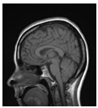

| Original Image | Marked Image | Encrypted Image (Chaotic) | Decrypted Image | Correlation between Extracted Blocks and Original Blocks |

![]() | ![]() PSNR = 35.99 dB SSIM = 0.97 | ![]() PSNR = 12.17 dB SSIM = 0.1035 | ![]() PSNR = 35.99 dB SSIM = 0.97 | ![]() |